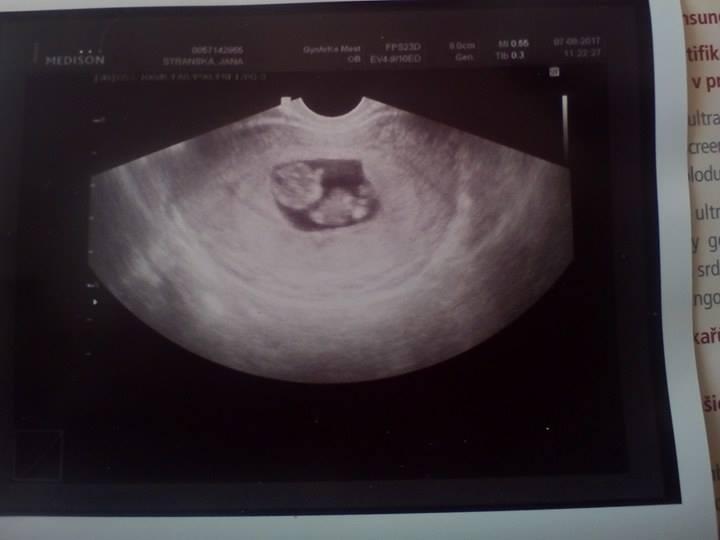

Ahoj holky ,potrebuju na dálku podpořit a obejmout ;( dnes mi přišla od mého gynekologa sms , ze se mam dostavit , ze výsledky mých testu nedopadly nejlépe ( Tripple testy ) . Dal mi zadanku do gennetu s tim , ze je nějaký problém se srdickem miminka .. víc neřekl .... mate nějaká zkušenost s těmito hodnotámy z toho Tripple testu ? Hodnota Free-hCG1 81 uz/L 2,42 MoM .... ma gennetu plno , jdu az 23.8. takže si asi umíte představit tu moji nervozitu a strach ...jinak první screening dopadl Dobre . Riziko Downa 1:49000 a riziko NTD 1:3000 .... díky holky 😱😪